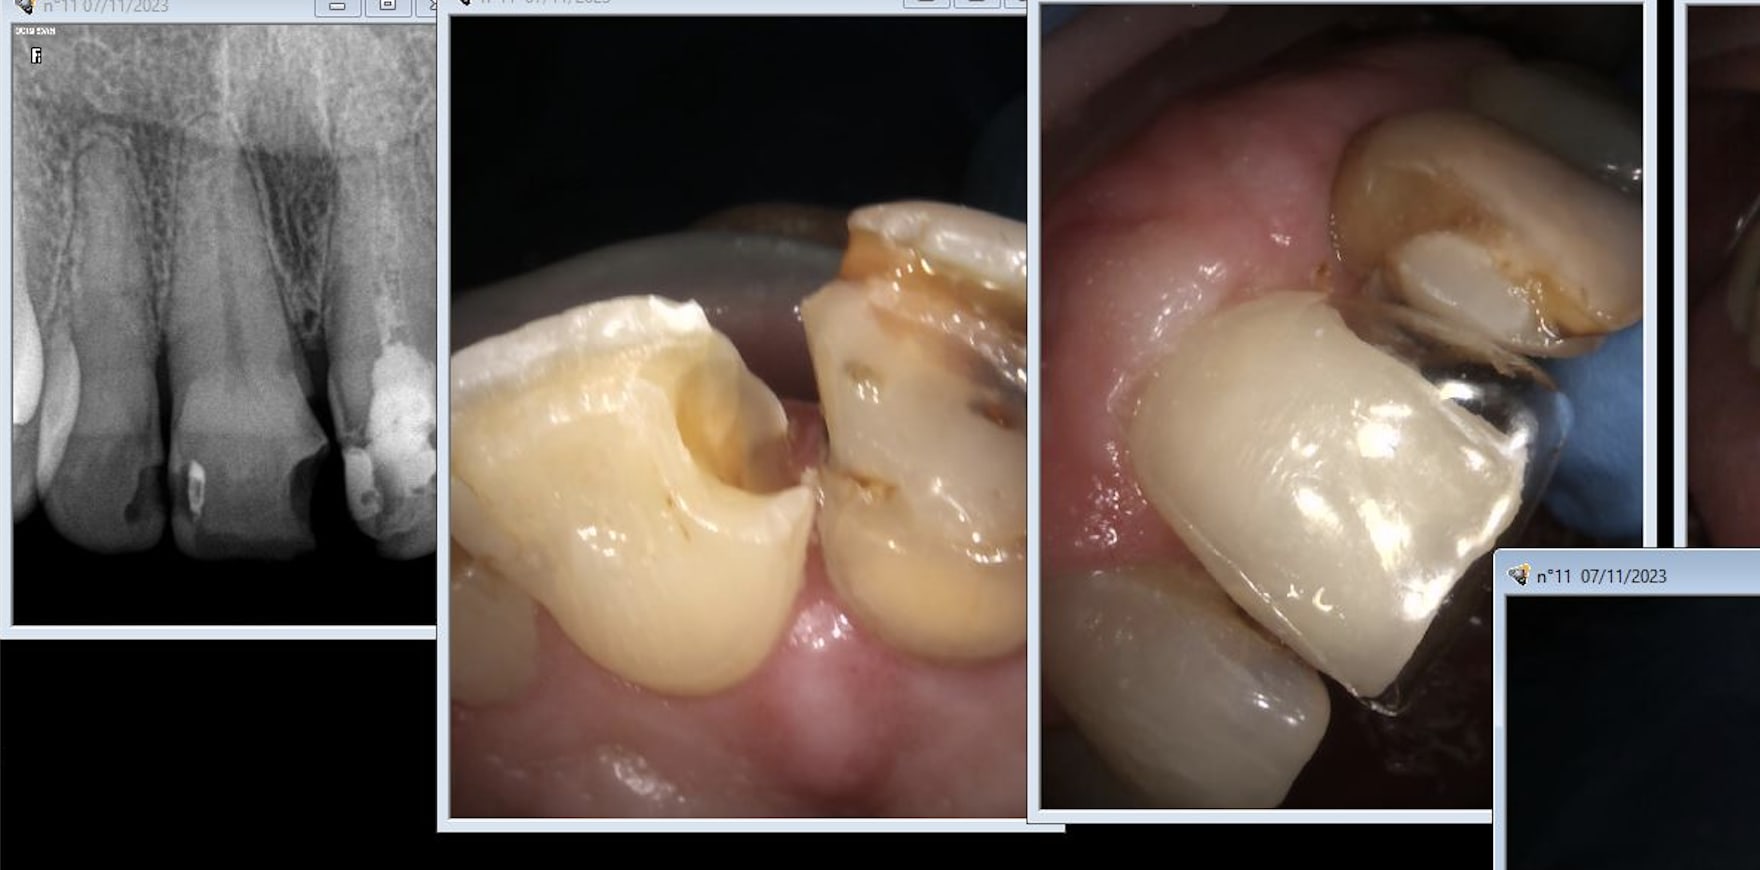

Keeo2bg0034razi05c8857kh03iu - Eugenol

P193y294hl6wqhi0zn6o5v160hbz - Eugenol

Ehxg942g1g6ouydi7ffyup336rcb - Eugenol

L'endo de 21 très couleur collectiviste locale. Encore un canal calcifié. Il y a casa qui va te dire que c'est top pas de 4ième aux innocents les mains pleines. -)